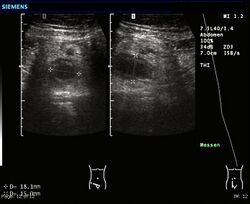

Abdominal ultrasonography, preferably with doppler sonography, is useful to detect appendicitis, especially in children. Ultrasound can show the free fluid collection in the right iliac fossa, along with a visible appendix with increased blood flow when using color Doppler, and noncompressibility of the appendix, as it is essentially walled-off abscess. Other secondary sonographic signs of acute appendicitis include the presence of echogenic mesenteric fat surrounding the appendix and the acoustic shadowing of an appendicolith.[55] In some cases (approximately 5%),[56] ultrasonography of the iliac fossa does not reveal any abnormalities despite the presence of appendicitis. This false-negative finding is especially true of early appendicitis before the appendix has become significantly distended. Also, false-negative findings are more common in adults where larger amounts of fat and bowel gas make visualizing the appendix technically difficult. Despite these limitations, sonographic imaging with experienced hands can often distinguish between appendicitis and other diseases with similar symptoms. Some of these conditions include inflammation of lymph nodes near the appendix or pain originating from other pelvic organs such as the ovaries or Fallopian tubes. Ultrasounds may be either done by the radiology department or by the emergency physician.[57]

Ultrasound showing appendicitis and an appendicolith[58]